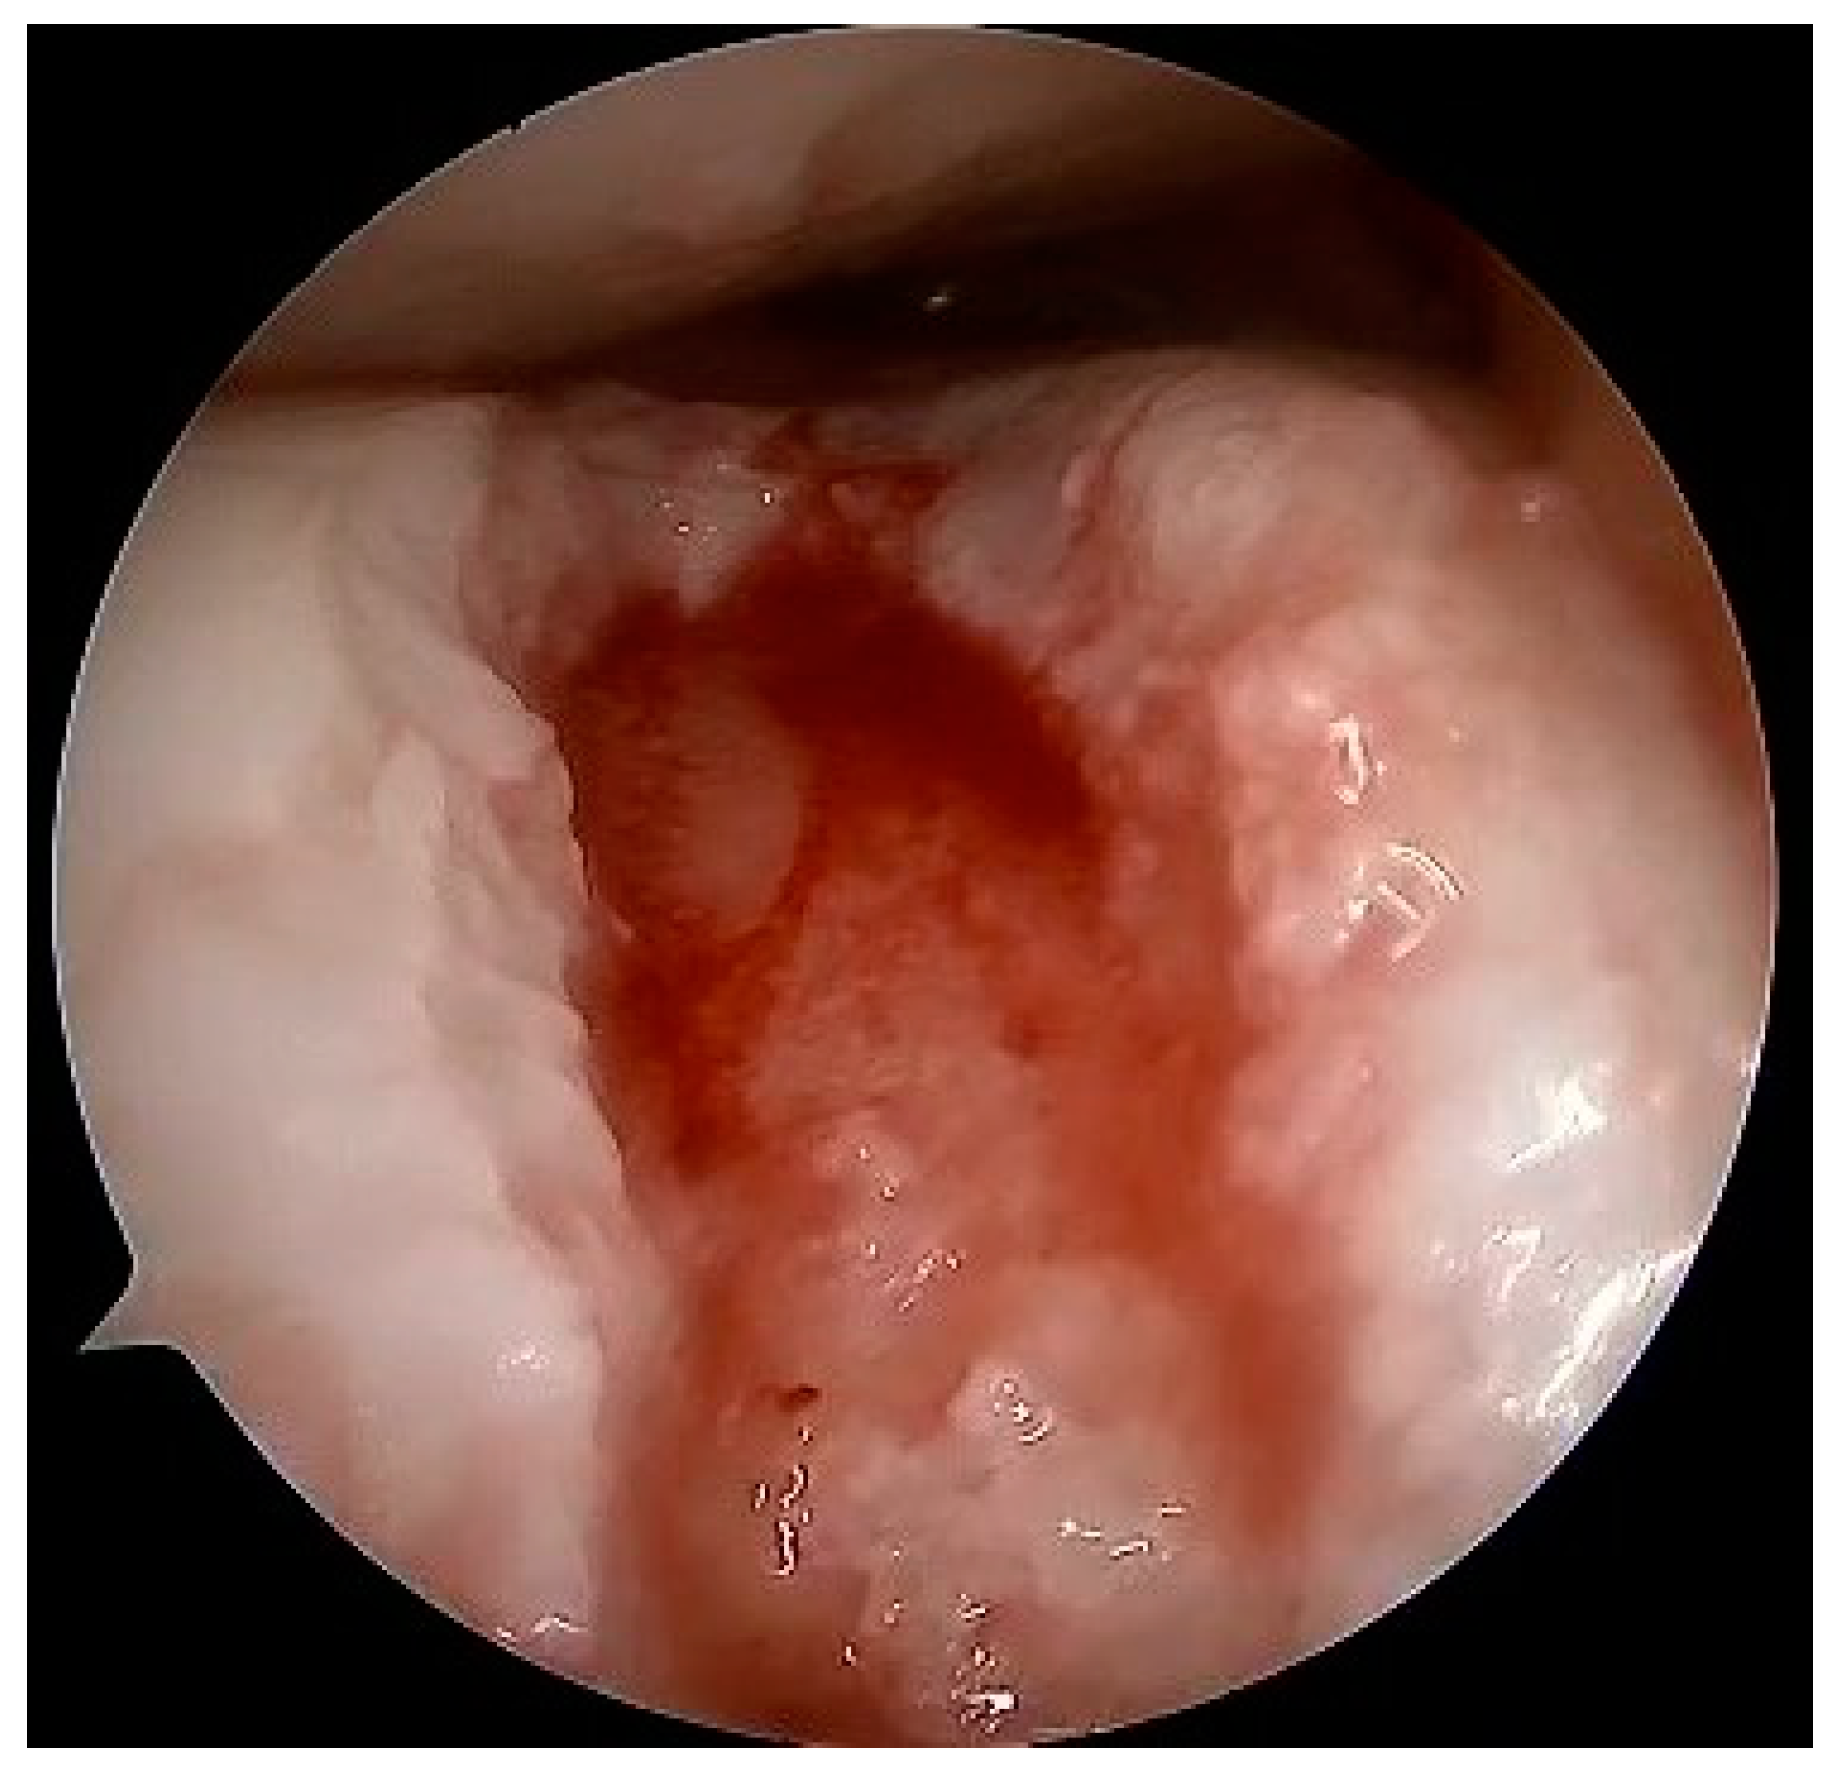

5.1. Microfracture

5.2. Autologous Matrix-Induced Chondrogenesis (AMIC)